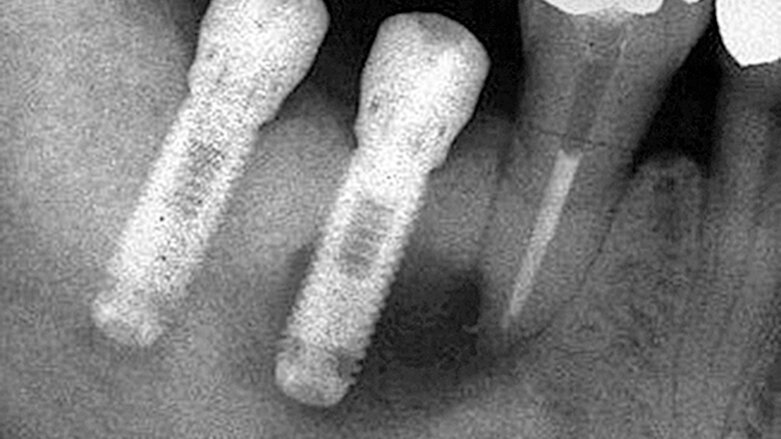

Obecně termín „periapikální léze u implantátu“ (PIL – periapical implant lesion) popisuje radiografický nález kolem apexu implantátu, bez vztahu k dalším periimplantátovým tkáním nebo sousedním zubům. Klinické vyšetření potíží pacienta nemusí vždy indikovat patologický nález, a pokud ano, tak se definice tohoto pojmu překrývá s „retrográdní periimplantitis“ (RPI – retrograde peri-implantitis). RPI má podobnou definici, ale je doprovázeno stížnostmi pacienta a často i klinickými nálezy (obr. 1–3).

RPI manifestuje skrze radiografické a také rozmanité klinické nálezy. V případě RPI je zde přítomna retrográdní infiltrace patologických mikroorganismů, které osídlí apex implantátu. Tato infiltrace často pochází od sousedního zubu, není to ovšem jediná příčina RPI. Další příčiny mají vztah k operačnímu protokolu, protetice a plánování implantace. Ve většině případů vede k diagnóze kombinace více než jednoho faktoru. Laterální defekty, mobilita implantátu a pooperační zánět vztahující se ke zbytku fixtury implantátu nebo zánět periimplantátových tkání jsou z této definice vyloučeny.

Jak PIL, tak RPI se často objeví jako náhodný radiografický nález až léta po zavedení implantátu a protetické rehabilitaci. Pokud jsou doprovázeny klinickými nálezy jako je pozitivní poklep, stížnosti na skus nebo syndrom bolesti, rozlišujeme dvě doby: a) po šesti týdnech od zavedení a b) čtyři až osm týdnů po zatížení. Stížnosti na bolest za delší dobu od zatížení jsou ve většině případů indikací křížové kontaminace od sousedních zubů.